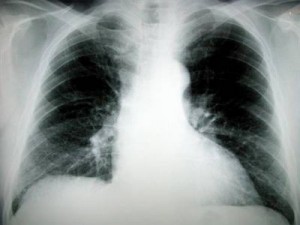

Researchers at OSU are bringing science fiction style nanomedicine into the real world. The research will give manufacturers the information they need to make an anti-lung cancer inhaler.

The work, submitted for publication this month, detailed the use Nanostructured(meaning particles only a few billionths of an inch across) Lipid Carriers (NLC) and their efficacy as a means for delivering cancer drugs via inhalation versus traditional intravenous(IV) delivery.

In the mice treated with the aerosol, an amazing 83% of the medication arrived where it was supposed to, in the tumors in the lungs. The effects were truly astounding tumors were shrunk from 40 cubic millimeters to less than 5. In 50% of the trials with the NLCS the tumors were reduced to such an extent that the researchers could not find them.